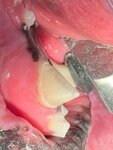

Огромное спасибо Дмитрию Остроухову за проведенные операции по спасению зуба собаке! Даже представить не мог, что так хорошо можно восстановить сломанный зуб, все выполнили отлично! В самой клинике приятный персонал, вежливые врачи и ассистенты, в приемных и коридорах чисто, опрятно. Определенно рекомендую!

Всегда обращались с Ветман по всем вопросам, связанными с питомцами. Однажды у нашего кота сильно ухудшилось самочувствие, он перестал кушать. Мы решили сразу же обратиться к стоматологу Дмитрию Антоновичу и выяснили что необходимо удалить все зубы. Коту 14 лет, разумеется, что нам было безумно страшно и крайне волнительно отдавать котейку в возрасте на полноценную операцию под наркозом. Провели консультации со специалистами по анестезии и кардиологии и пришли к выводу, что всё должно быть хорошо, удаление зубов необходимо всё-таки произвести. Приятно удивило, что нас держали в курсе по ходу операции и быстро нам отвечали на все вопросы. Высылали фото и комментировали что, как и зачем. Удаление зубов было проведено успешно, после чего нам порекомендовали всё, что нужно делать и поддерживали по ходу всего восстановления кота. ОГРОМНОЕ человеческое спасибо анастезиологу Егору Сергеевичу и стоматологу Дмитрию Антоновичу- вы наши герои, сделавшие жизнь нашего любимца гораздо лучше! ❤️